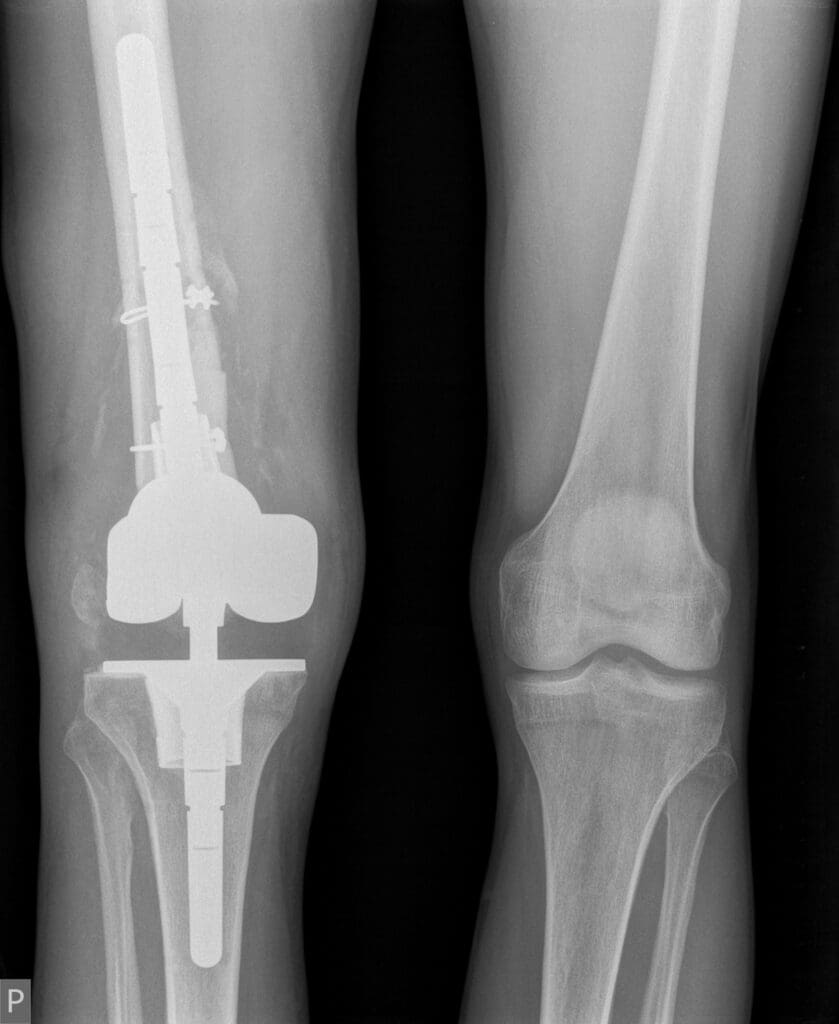

Po ustabilizowaniu najgroźniejszych obrażeń konieczne było przeprowadzenie kilku poważnych operacji ortopedycznych. Jednym z najtrudniejszych wyzwań było zrekonstruowanie kolana, które w wyniku wypadku uległo niemal całkowitemu zniszczeniu. Fragmenty kości uległy martwicy i rozpadowi, co znacząco utrudniało możliwości dalszego leczenia.

Lekarze z Kliniki Urazowo-Ortopedycznej pod kierownictwem dr. Rafała Wójcickiego przeprowadzili innowacyjny zabieg rekonstrukcji stawu kolanowego, stosując nowoczesne materiały i cement kostny. Było to kluczowe dla dalszej terapii, ponieważ umożliwiło odbudowę ubytków kostnych i przygotowanie pacjenta do kolejnych etapów leczenia.

Po kilku miesiącach rehabilitacji przystąpiono do kolejnego zabiegu – usunięcia czasowej protezy i wszczepienia endoprotezy stawu kolanowego. Dzięki nowoczesnym implantom udało się przywrócić funkcjonalność kończyny.